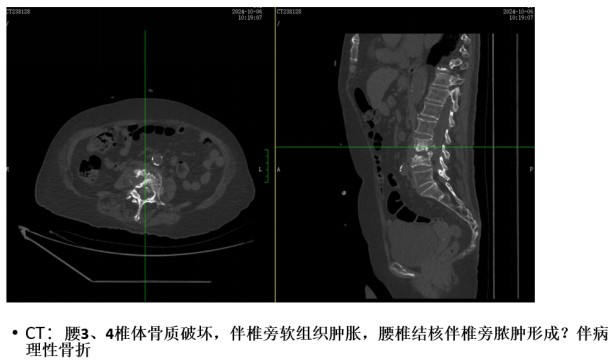

為解決老人病痛,脊柱外科錢軍博士團(tuán)隊(duì)對其進(jìn)行了詳細(xì)的查體以及全面細(xì)致的評估,診斷為L3、4脊柱結(jié)核伴病理性骨折、椎旁膿腫,患者腰部疼痛癥狀逐漸加重,病灶已經(jīng)壓迫神經(jīng)引起了截癱。